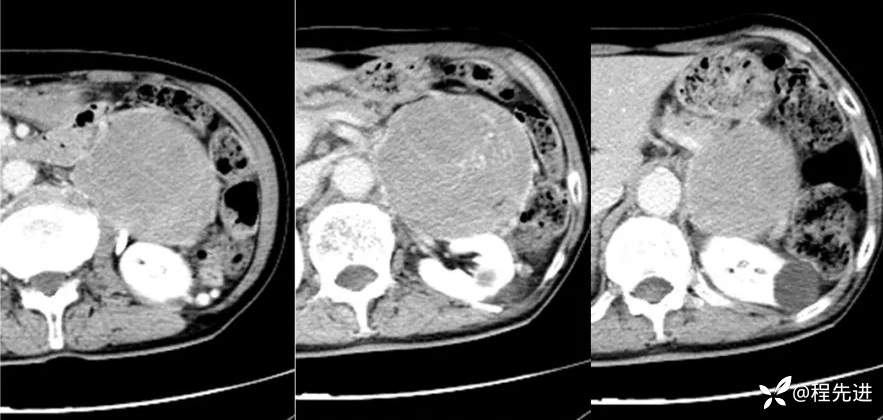

CT增强:

延迟期: